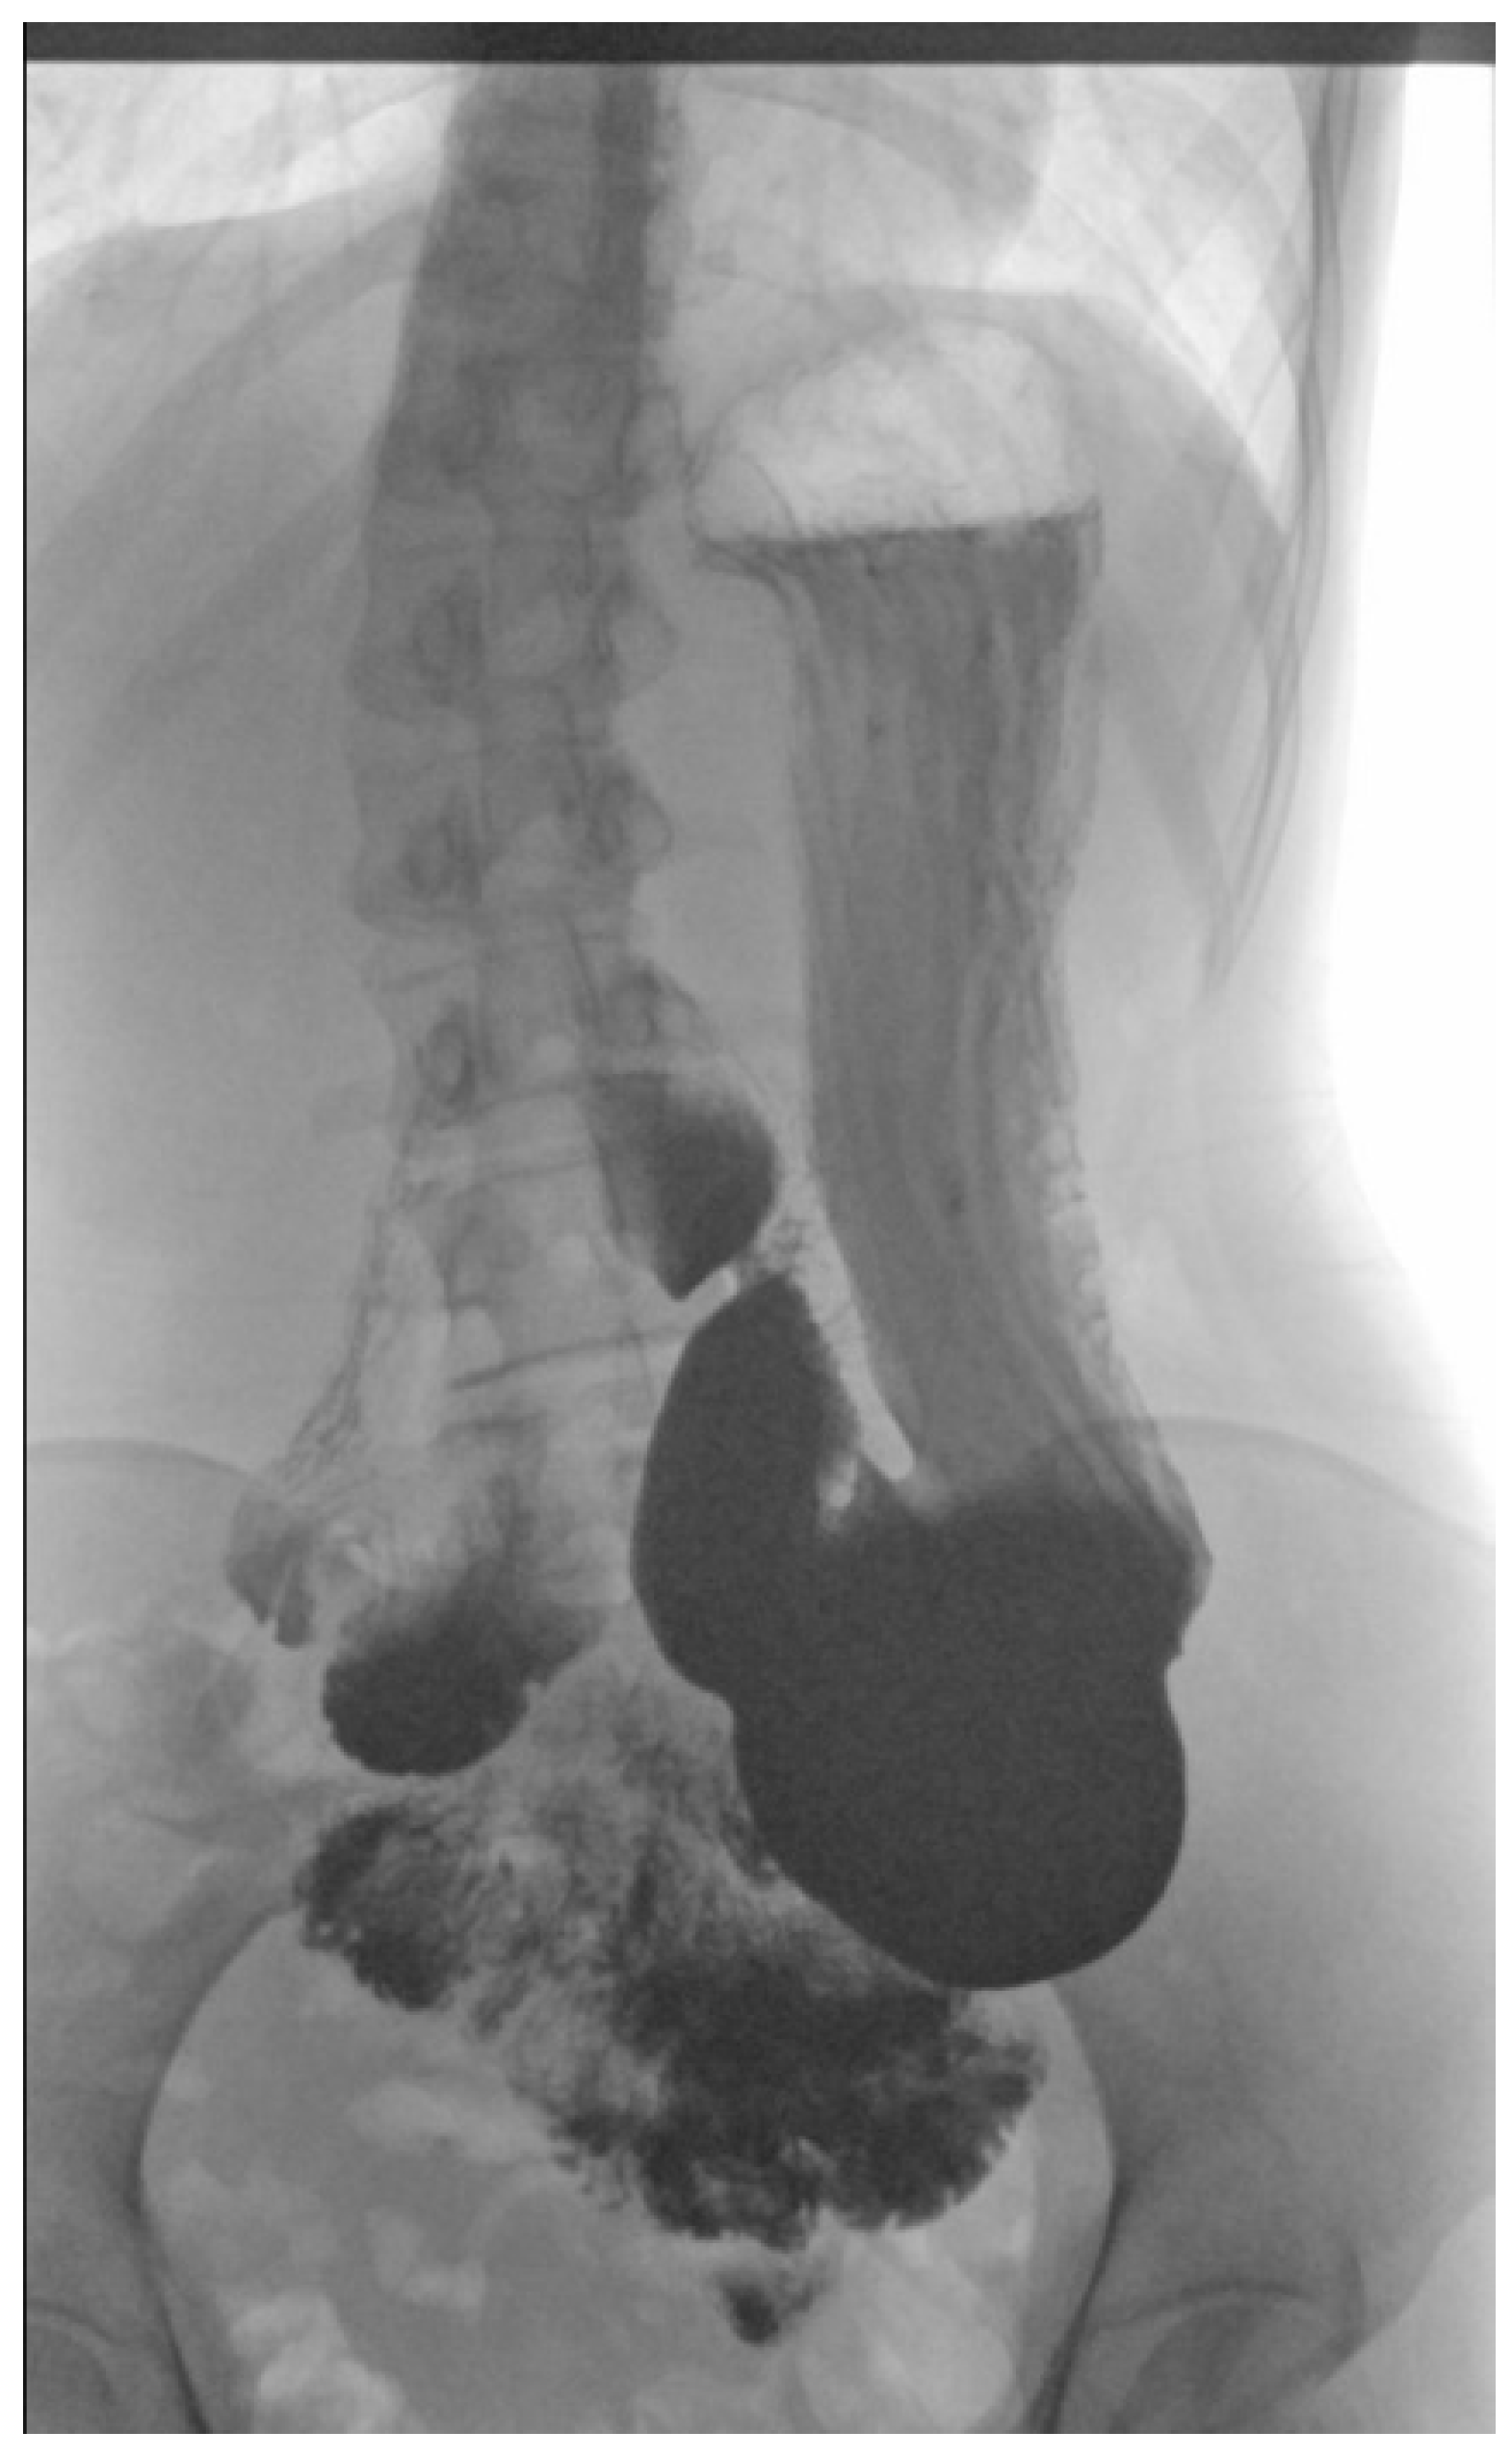

2.4. Physical Examination, Laboratory Tests’ Results and Imaging Studies

2.5. Diagnosis and Treatment